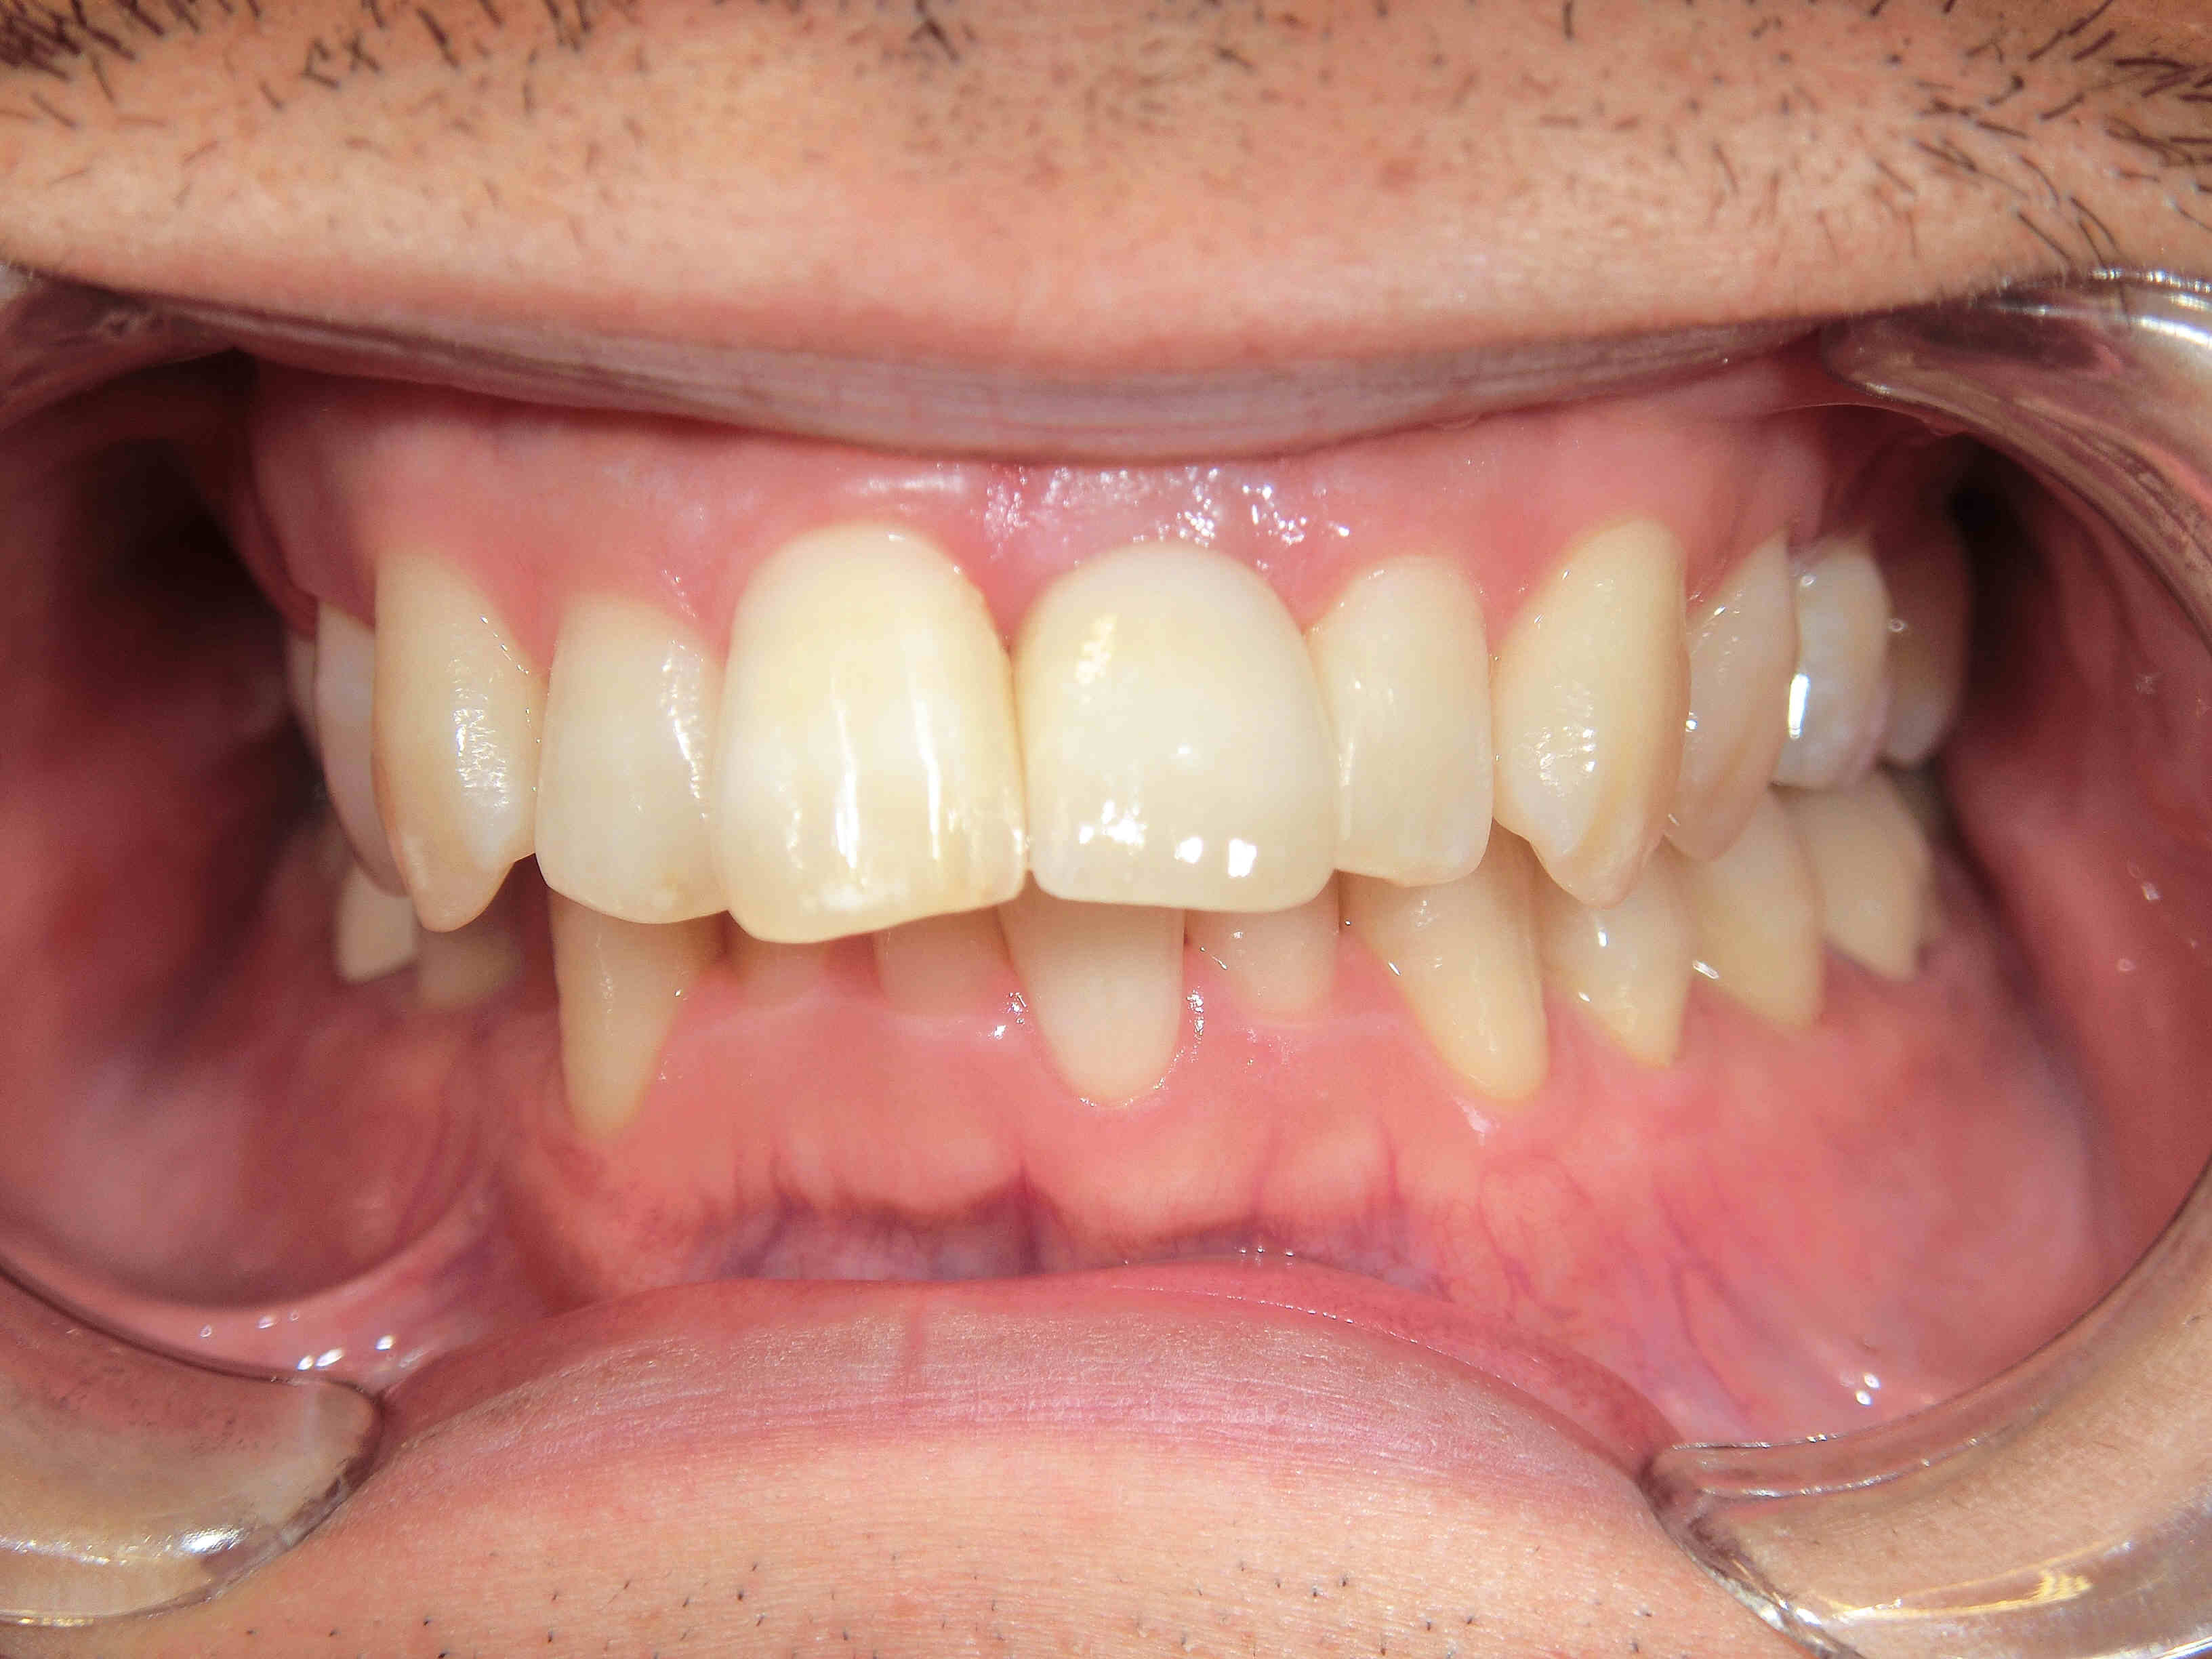

上記写真は、治療前の状態です。